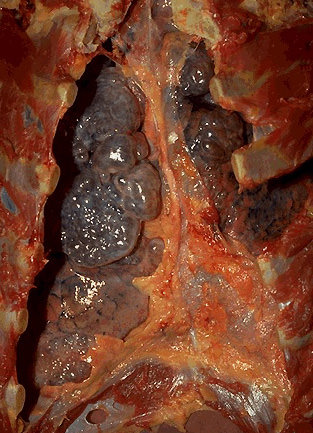

Для таких вот самоотверженных курильщиков, не щадящих живота своего, мы и представляем ряд наглядных материалов, иллюстрирующих изменения, происходящие в организме курящего человека. Быть может просмотр этой подборки заставит кого-то задуматься о том, во что превращается ваш организм под влиянием сигарет.

Удаленная раковая опухоль